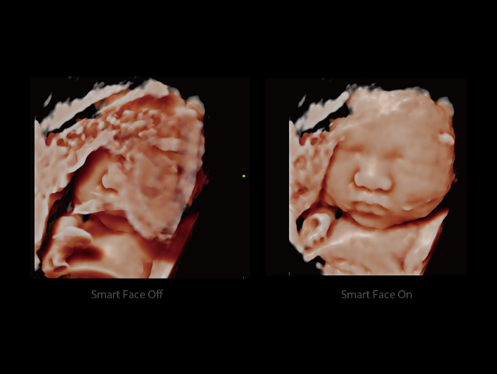

Experiencia eXtraordinaria

Experiencia con alta productividad

La innovaciГіn inspirada e impulsada por las necesidades clГӯnicas. El DC-80A con X-Insight se centra en lo que importa y perfecciona su experiencia de usuario con una mejor ergonomГӯa, escaneo mГЎs fГЎcil y una administraciГіn flexible, incluso mГЎs allГЎ de sus expectativas.